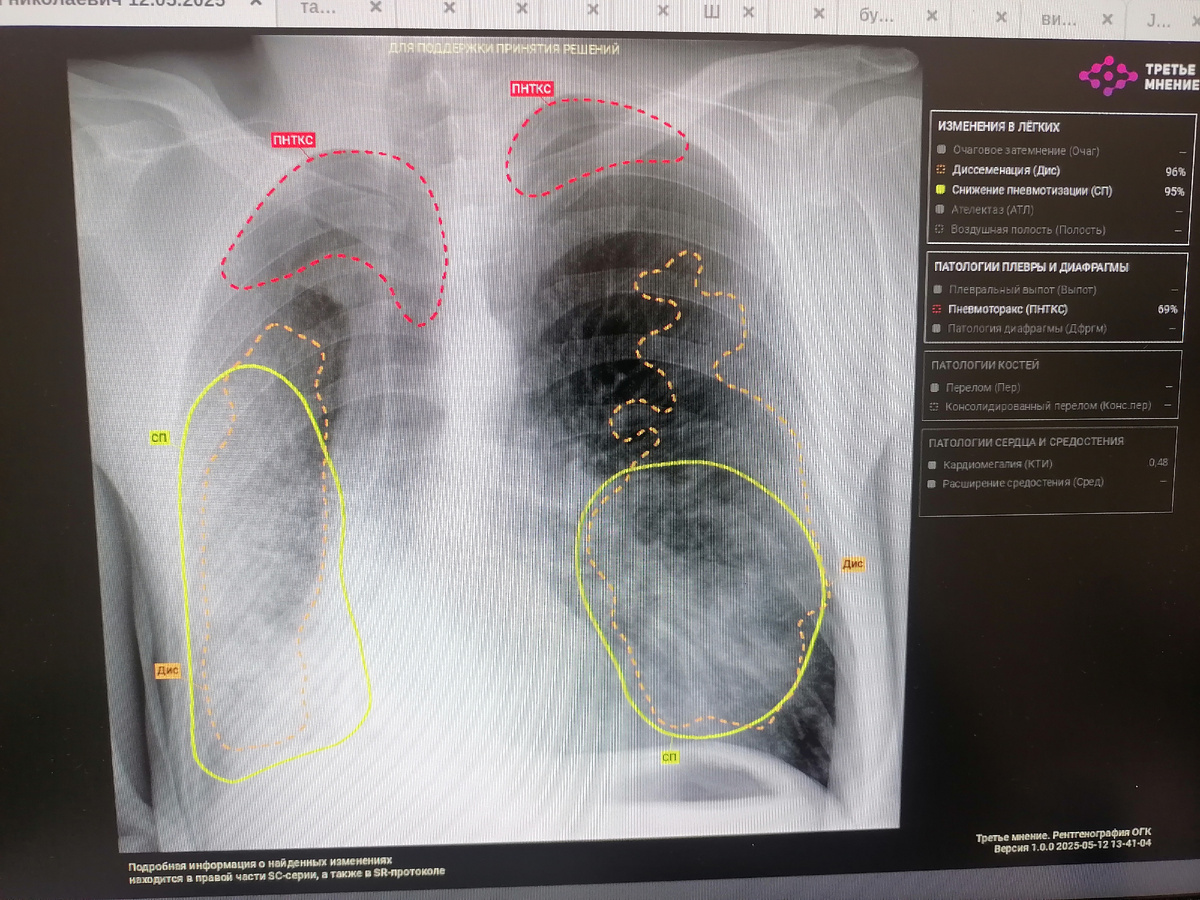

ИИ разбивает анализируемое изображение на фрагменты, преобразует их в математические символы, сопоставляет их со своими шаблонами из базы данных. Если находит совпадение с патологическим паттерном, система выделяет патологическую область определенным цветом. Паттерны- это закономерности, характерные для какого- либо заболевания ( например, текстура, форма, цвет, плотность, граница опухоли).

Так называемая "тепловая карта", где разными цветами подсвечены патологические участки.